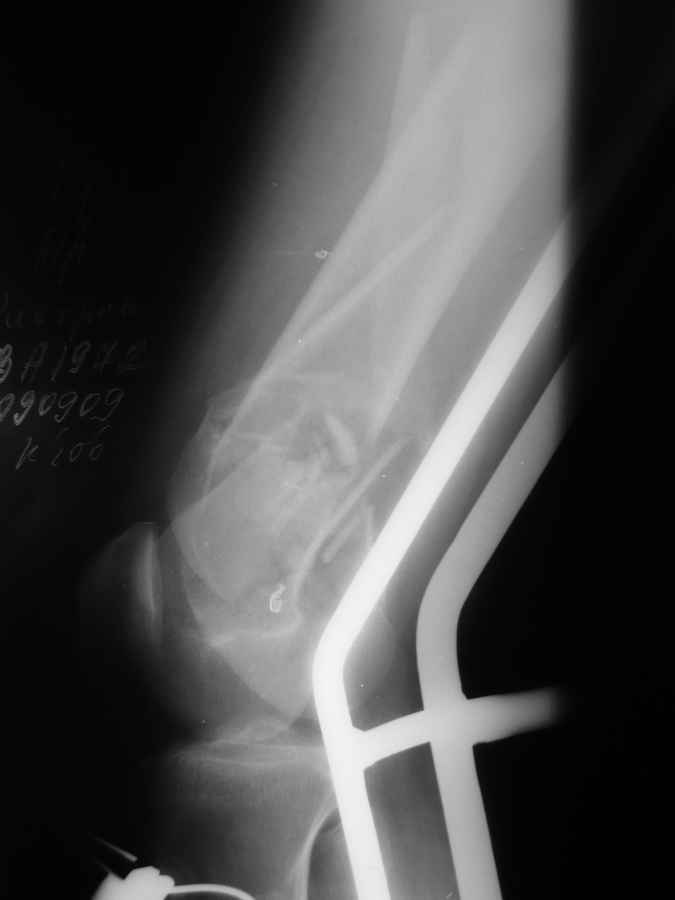

Это перелом не нижней трети, а дистального суставного конца, с распространением на диафиз. Что-то между C2 и C3. Но пока ближе к C2 по увиденному - вторую проекцию еще не показали.

На профиле стало видно, что открываться придется, это перелом C3, хотя можно назвать и C2+, т.е. с еще и фронтальным раскалыванием одного мыщелка. Надо сделать медиальную артротомию, ступеньку на внутреннем мыщелке устранить, ввести либо несколько временных спиц спереди назад, или сразу винт вдоль эллипса мыщелка. А дальше как выше написано - дистрактор, и штифтовать. Учитывая наличие открытого колена - вполне уместно ретроградно.